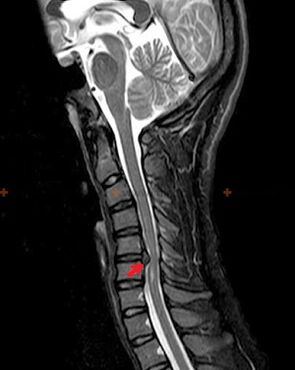

Osteochondrosis is an x-ray diagnosis, since a detailed clinical picture is available only at the time of deterioration, while changes in the spine can occur with the complete subjective well-being of a person.Without an X-ray examination, we can only talk about suspected osteochondrosis, because similar symptoms can be caused by other diseases (myositis, vertebral neoplasms and others).

To diagnose osteochondrosis, the following research methods are used: X-ray (possibly with functional tests), MSCT and MRI.The last study is the most preferred due to the fact that it allows one to visualize very clearly the state of the intervertebral structures.

The presence of the changes described above, as well as changes in the structure of the intervertebral disc, detected by MSCT and MRI, serve as reliable signs that confirm the presence of osteochondrosis.